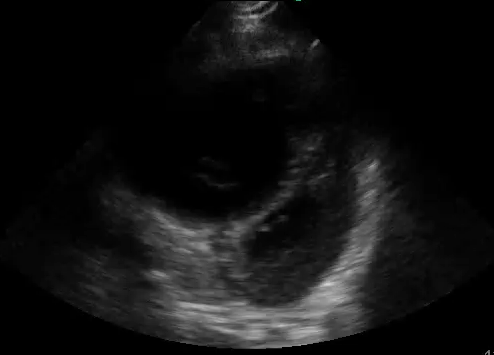

Image Acquisition: Basic Focused Assessed Transthroacic ECHO (FATE) was performed (See videos below).

Image Interpretation: Pericardial effusion was absent yet the right ventricle (RV) was dilated acutely as the RV wall thickness was normal (subcostal).  The systolic D-septum (parasternal) suggested an elevated RV afterload.  Along with the hyperdynamic left ventricle (LV) and normal left atrium (LA), there was likely a flow obstruction between the RV to LA which maybe related to the “lesion” in the RV.

The four basic cardiac views were attained though the quality varies with the apical 4 view being the least favourable with the patient in an upright position and taking rapid breaths. In practice, especially during acute situations, positioning for the ideal windows may not be feasible; and, often, not all windows can be obtained.

The first and foremost PoCUS interpretation parameter to answer is whether quality of the acquired images is adequate: pristine to unreadable. The images attained were not ideal: the septum of the parasternal long view was not horizontal; the apical 4 view was off axis; and etc… Nevertheless, they sufficed to answer the author’s clinical questions (indications).

“Lesions” and “things” may sometimes be seen in the cardiac chamber as per in this case. It can be thrombus, vegetation – infected or sterile, tumour, or foreign body. There are certain ultrasonographic features that may suggest one differential over another though this differentiation is not the role of PoCUS. In this case, one can only conclude that there is something inside the RV.